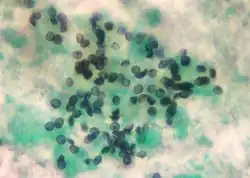

| Pneumocystis jirovecii cysts from bronchoalveolar lavage, stained with Toluidine blue O stain | |

The diagnosis can be definitively confirmed by histological identification of the causative organism in sputum or bronchoalveolar lavage (lung rinse). Staining with toluidine blue, silver stain, periodic acid-Schiff stain, or an immunofluorescence assay shows the characteristic cysts.[13] The cysts resemble crushed ping-pong balls and are present in aggregates of two to eight (and not to be confused with Histoplasma or Cryptococcus, which typically do not form aggregates of spores or cells). A lung biopsy would show thickened alveolar septa with fluffy eosinophilic exudate in the alveoli. Both the thickened septa and the fluffy exudate contribute to dysfunctional diffusion capacity that is characteristic of this pneumonia.